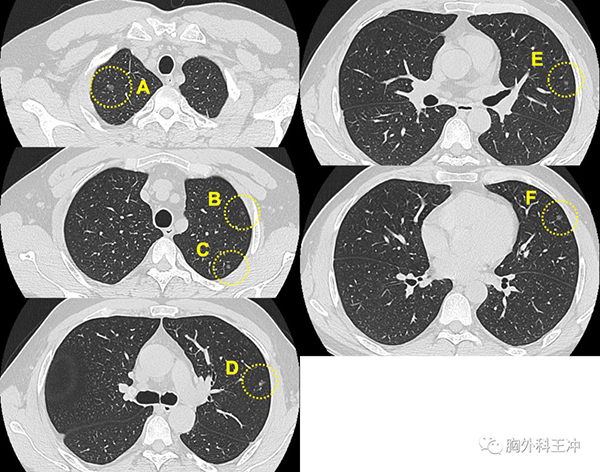

基本情况 女性,65岁,2013年体检发现双肺多发磨玻璃结节,未行治疗,今年复查几乎所有结节均增大,有新发结节。

手术方式 VATS右肺上叶切除、淋巴结清扫术

病理结果 病灶A 浸润性腺癌,1.5cm,贴壁型60%,腺泡型20%,乳头型20%

病灶D 微浸润腺癌,0.7cm,浸润直径0.2cm

基因检测 未做

手术理由 1、多发磨玻璃结节均明显增大;

2、右肺上叶较大者,范围扩大、实性成分增加,应优先处理;

3、右肺上叶结节最多,宜优先处理;

故进行右肺上叶切除。

下一步治疗 行基因检测,定期复查